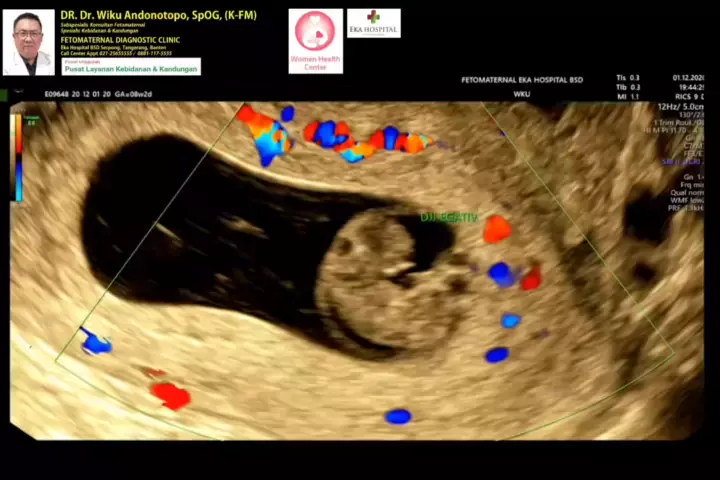

Kematian Embrio 8 minggu... #fetomaternalbatam #fetomaternalmanado #fetomaternalmakassar #usgfetomaternalpontianak #konsultanfetomaternalpontianak #fetomaternalrsiafamilypluit #fetomaternalgrandfamilypik #fetomaternalmalang #usgfetomaternaltangerang #usgfetomaternalbekasi #usgfetomaternalcibubur #usgfetomaternaljakarta #konsultanfetomaternaltangerang #konsultanfetomaternalcibubur #konsultanfetomaternalbekasi #konsultanfetomaternaljakarta #kehamilansehat #fetomaternalpekanbaru #ceritahamil #eduk... More